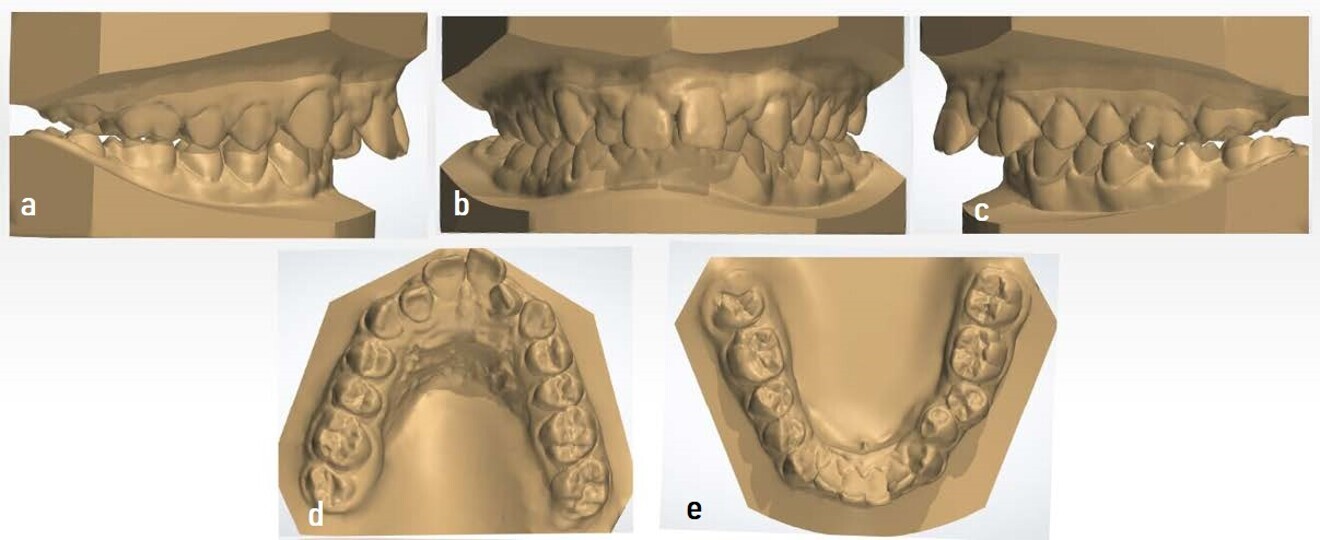

In the model analysis, the same results as seen in the intra-oral analysis were observed. The dental models were scanned with iTero (Align Technology) for their subsequent digitisation and study (Fig. 8). This facilitated the data collection and interpretation, as well as the confirmation of an 11 mm overjet. The models were measured with 3Shape Dental System. Records were taken for subsequent comparison with the final models after the treatment.

Figs. 8a–e: Initial digital models showing a bilateral Class II malocclusion and an overjet of 11 mm (images generated using 3Shape Dental System).